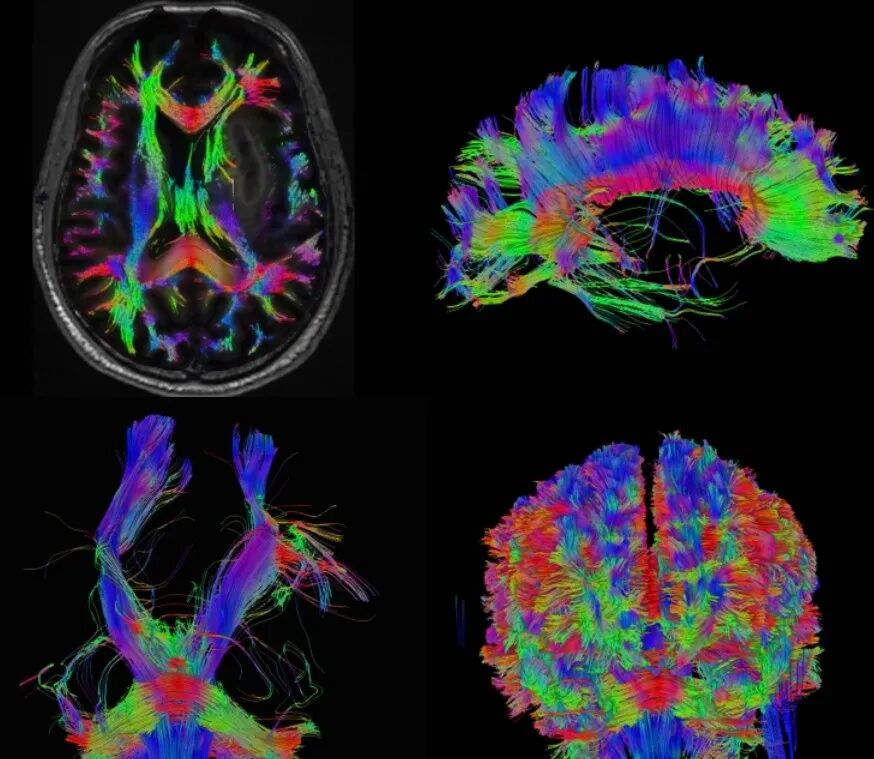

DTI 和 BOLD

弥散张量成像(DTI)和血氧水平依赖功能成像(BOLD)联合应用可以显示神经纤维传导束,并能较准确地反映脑功能区,对颅内肿瘤的术前评估和术后随访具有指导意义。